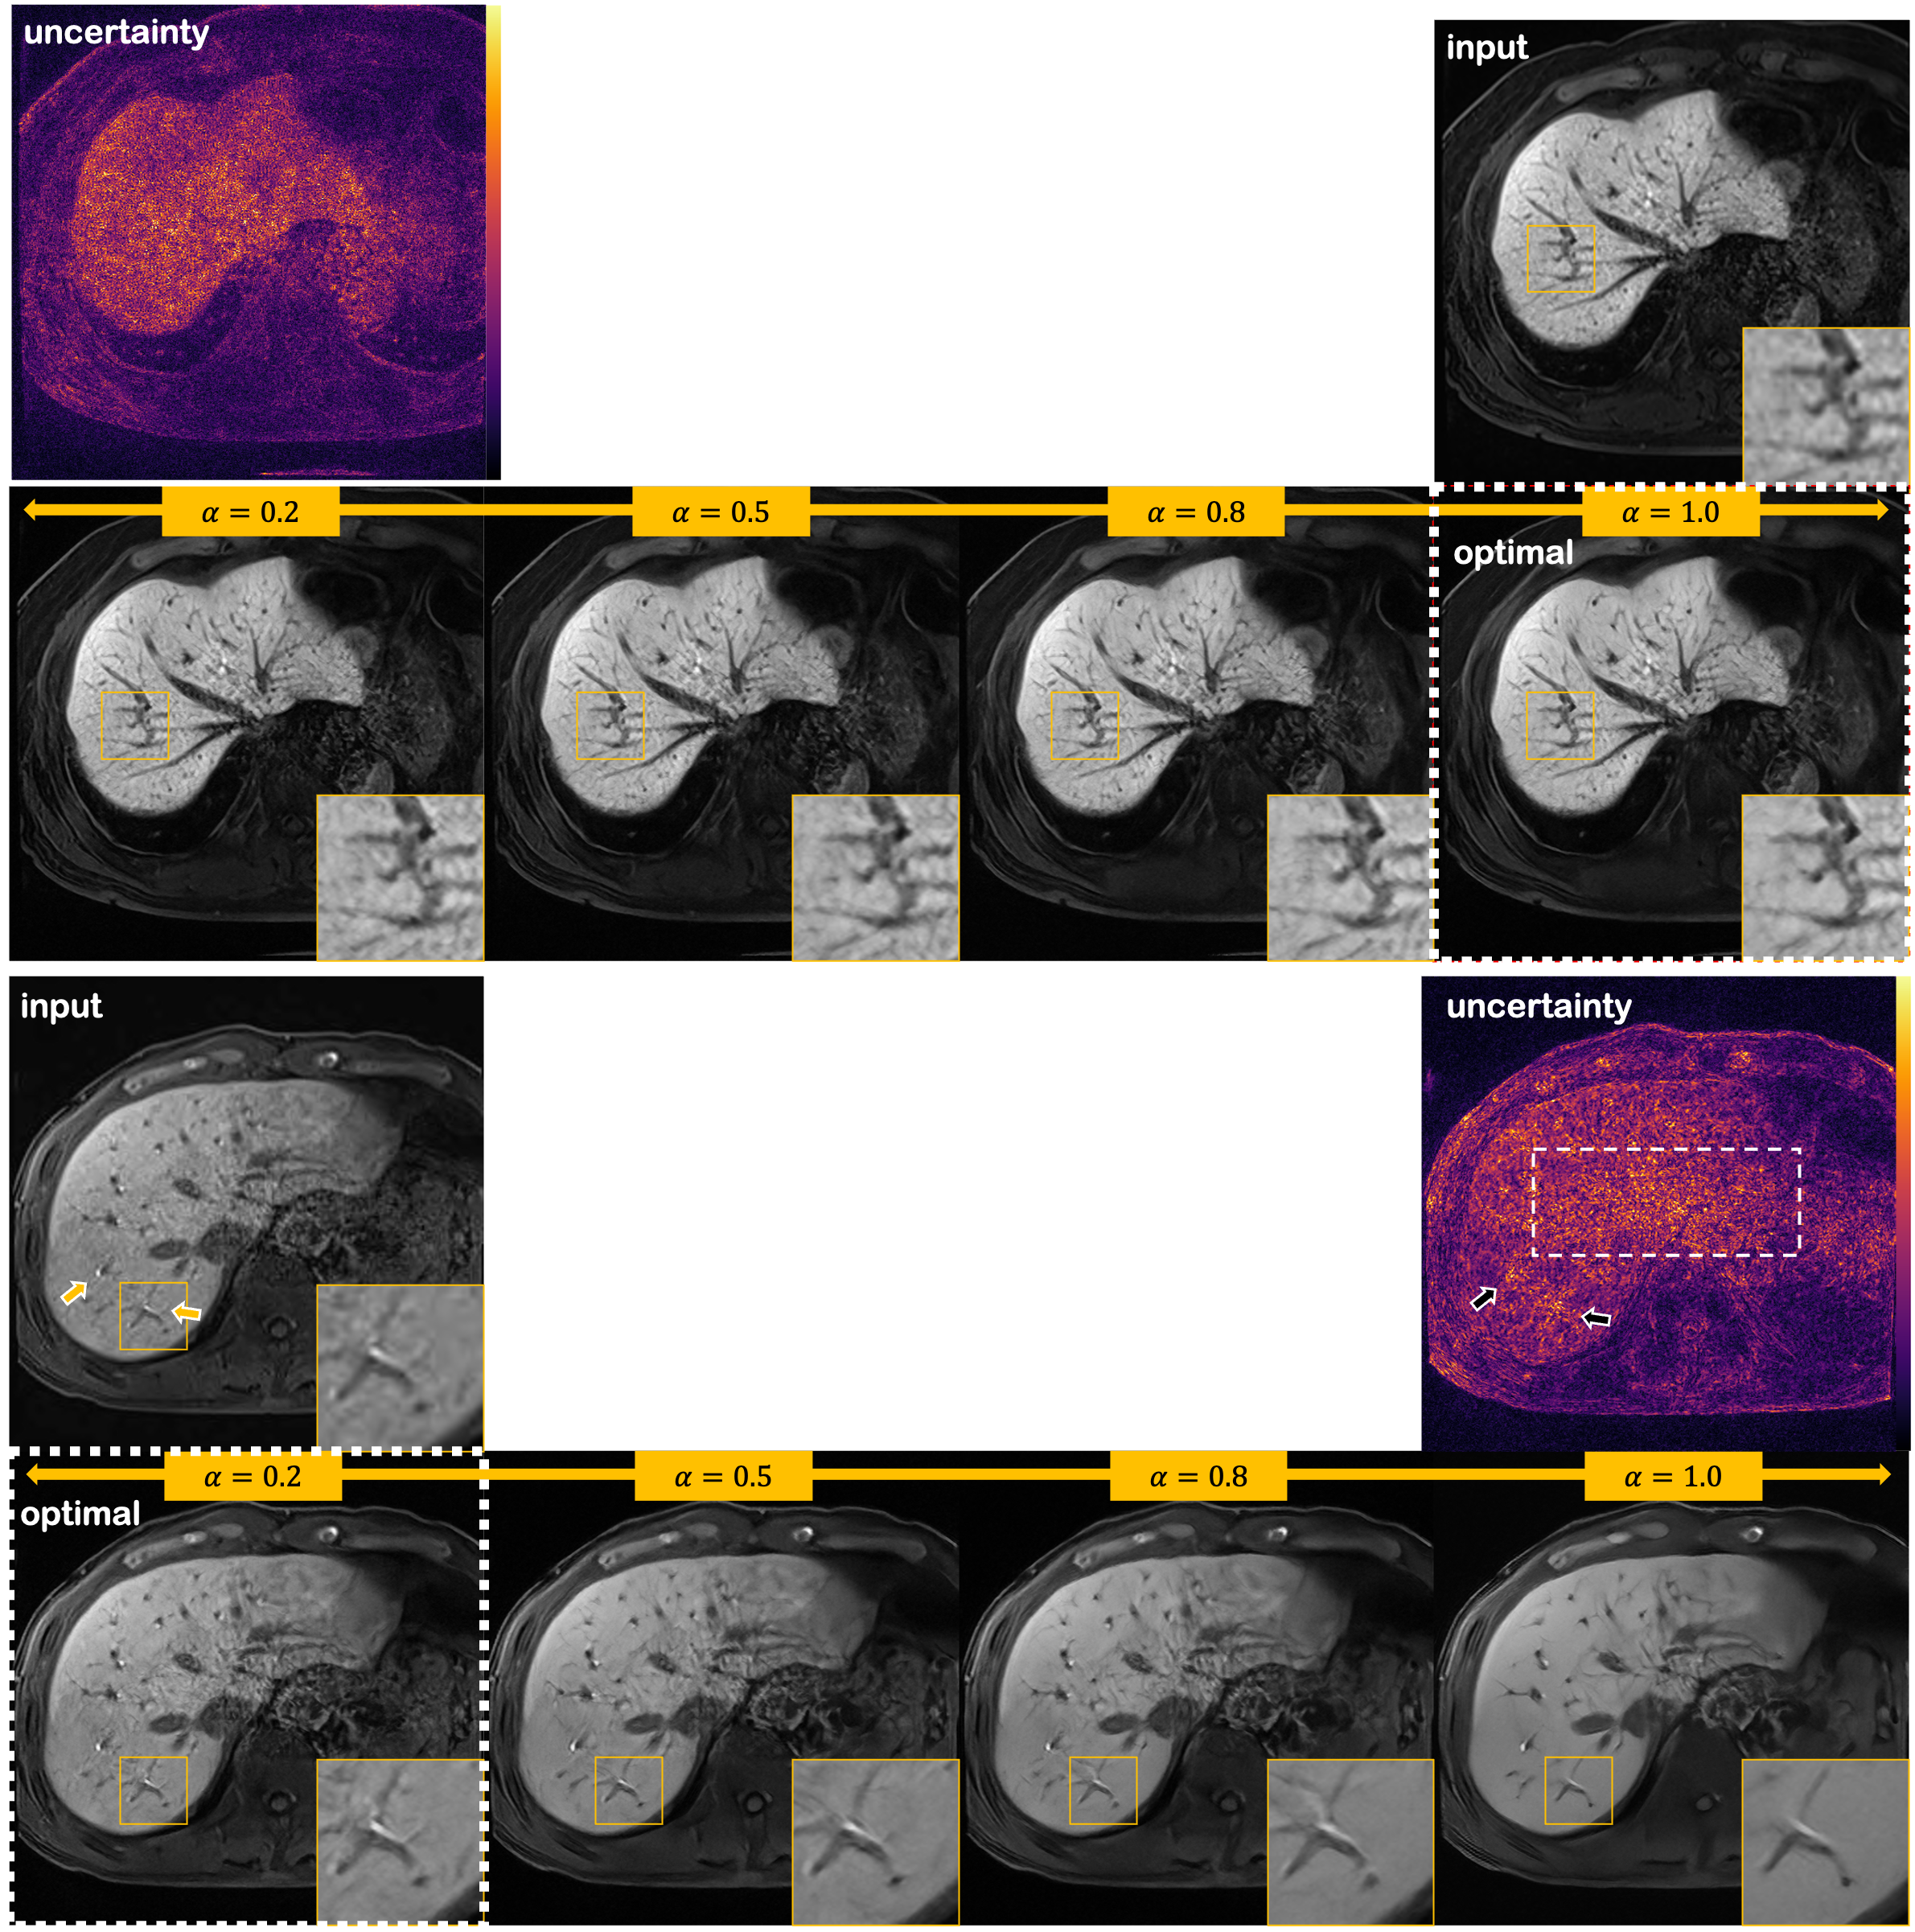

Refer to caption

Figure 4: Illustration of flexibility and uncertainty estimating property of the proposed method for the two patient data. In the first row of each data, input noisy image and uncertainty map (standard deviation of the posterior mean) are shown. The second row illustrates denoised results with varying values of α𝛼\alpha. The arrows indicate regions of high uncertainty, and the white box with dotted line points out region with concentrated noise. White boxes with the dotted line indicate the values of α𝛼\alpha used to compute the posterior mean.

V-B Flexibility and uncertainty

As was discussed earlier, we can flexibly adjust the parameter α𝛼\alpha so that we can get just the right amount of denoising that we want. An illustration of such control is shown in Fig. 4, where we vary the value of α𝛼\alpha from 0.20.20.2 to 1.01.01.0.

In the first sample, it is clearly seen that we are able to achieve better results with higher values of α𝛼\alpha. With a lower factor, the noise is insufficiently removed. This is the case where noise is distributed in a holistic manner, and hence the noise distribution is closer to the Gaussian distribution (see the input image). Since our noise estimator [26] is able to estimate the noise variance with high accuracy in this case, we do not have to alter the estimated value and simply set α𝛼\alpha close to 1.01.01.0.

On the other hand, in the second sample, we see that with a high value of α𝛼\alpha, the texture and the important details of the liver are washed out, and hence it would be better to keep the denoising factor α𝛼\alpha at a low level. Notice that pulsation artifact [49] is apparent in the central region of the image, also clearly seen in the input image. In such cases, the periphery of the image is rather clean, whereas the central region of the image is contaminated with very high scale of noise. Hence, it can be seen that the distribution of noise is far from Gaussian, leading to an over-estimation of the noise variance. Therefore, lower values of α𝛼\alpha may be needed. In any case, being able to control the amount of denoising is a prominent feature of our proposed method, and would be of great importance in clinical settings.

Another important feature of the proposed method is the ability to quantify uncertainty. Denoising is an inverse problem, and hence there can be many feasible solutions. In order to embrace this fact, prior works have proposed several ways to estimate the uncertainty. For instance, [50] leveraged MC dropout [51]. Other works tried to estimate the variance directly [52]. In contrast, with the proposed method, we can simply sample multiple posterior samples, and directly compute the statistics from these samples. In order to show such property of R2D2+, we took 5 different posterior samples given the noisy image, and computed the mean and the standard deviation of the samples. The results are shown in the uncertainty maps of Fig. 4. The first sample does not depict any excessive variance in specific regions, and hence we can be fairly confident with the resulting denoised image. Contrarily, we do observe some regions of higher variance in the second sample (marked with arrows), which may indicate that a clinician should be conservative on decision making based on the denoised samples.